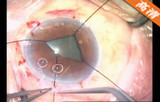

该手术透明角膜切口,注入粘弹剂 ,辅助切口;,连续环形撕囊;水分离、水分层; 超声乳化吸除晶状体核 ,灌注抽吸手柄(I/A)抽吸出残留的晶状体皮质; 后囊膜抛光 ,注入粘弹剂 。植入折叠人工晶体, 吸除医用透明质酸钠凝胶 ,水密切口 。